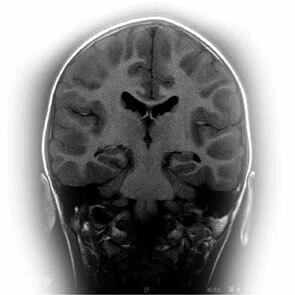

La pregnénolone est produite dans nos surrénales, dans notre cerveau et, également, dans notre système nerveux périphérique où elle pourrait avoir un rôle dans le maintien de la couche de myéline. Elle est également sécrétée dans la peau, les ovaires et les testicules. Elle est le point de départ de la cascade stéroïdienne. Elle est la première hormone à être issue de la transformation du cholestérol. La pregnénolone est un précurseur des minéralocorticoïdes (aldostérone), des glucocorticoïdes (cortisol), de la DHEA et de la progestérone. La pregnénolone et son métabolite le sulfate de pregnénolone sont également synthétisés dans le cerveau, d'où leurs noms de neurostéroïdes.

L'action de la pregnénolone sur la mémoire a été bien montrée aussi bien chez l'animal que chez l'homme. La pregnénolone est un antagoniste du GABA et un agoniste ou stimulateur des récepteurs NMDA (N-méthyl-D-aspartate) qui renforce le système des neuromédiateurs diminuant avec le vieillissement. La pregnénolone stimule également la synthèse de l'acétylcholine et ceci a été particulièrement bien démontré dans l'hippocampe.

Les actions de la pregnénolone

En revanche, les effets de la pregnénolone deviennent particulièrement intéressants pour la mémoire chez les personnes de plus de 50 ans. La pregnénolone est une des substances naturelles les plus actives pour stimuler et améliorer la mémoire chez l'animal. La pregnénolone bloque les effets inhibiteurs de l'acide aminé glycine et du GABA contribuant à l'équilibre de la balance inhibition / excitation du système nerveux central. Elle augmente le relargage de l'acétylcholine, puissant neuromédiateur, et agit sur les récepteurs NMDA (N-méthyl-D-aspartate) impliqués dans la mémoire.